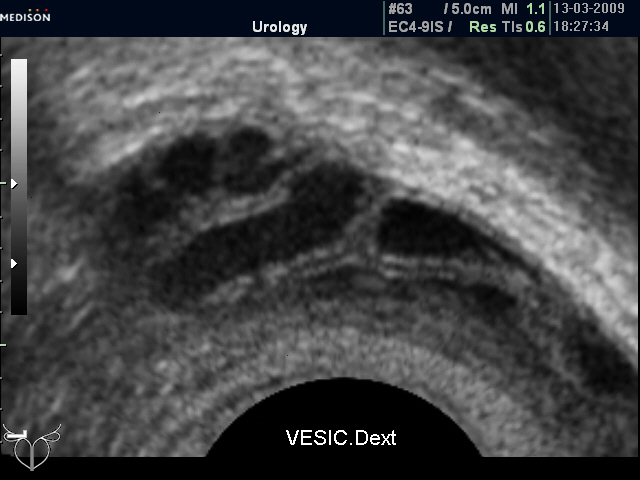

Но не всегда норма СП при ТА УЗИ подтверждается при ТРУЗИ (фото 3-6)

"Нормальные" СП (ТР УЗИ)